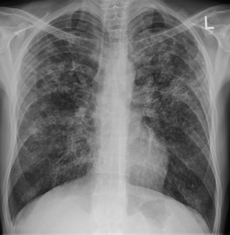

CXR

- Primary infection

- Infiltrates in any area of the lung

- Isolated hilar or mediastinal adenopathy may be only finding

- Reactivation infection

- cavitary/noncavitary lesions in upper lobe or superior segment of lower lobe

- Latent infection

- Upper lobe or hilar nodules and fibrotic lesions

- Ghon foci, areas of scarring, calcification

- Miliary TB

- Looks like millet seeds on CXR

- Immunocompromised patients less likely to have classic lesions and may have normal CXR